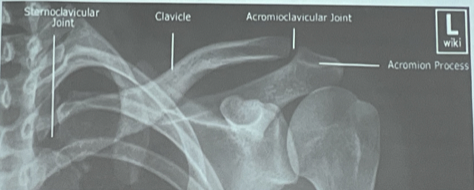

Articulaciones de la clavícula

Medial: esternoclavicular

Lateral: ligamentos coracoclaviculares y acriomioclavicular

¿Cuáles son todas las articulaciones del hombro?

1. Esternoclavicular

2. Acromioclavicular:

Ligamentos acromioclaviculares: Sup, inf, ant y post

Ligamentos coracoclaviculares: conoide, trapezoide